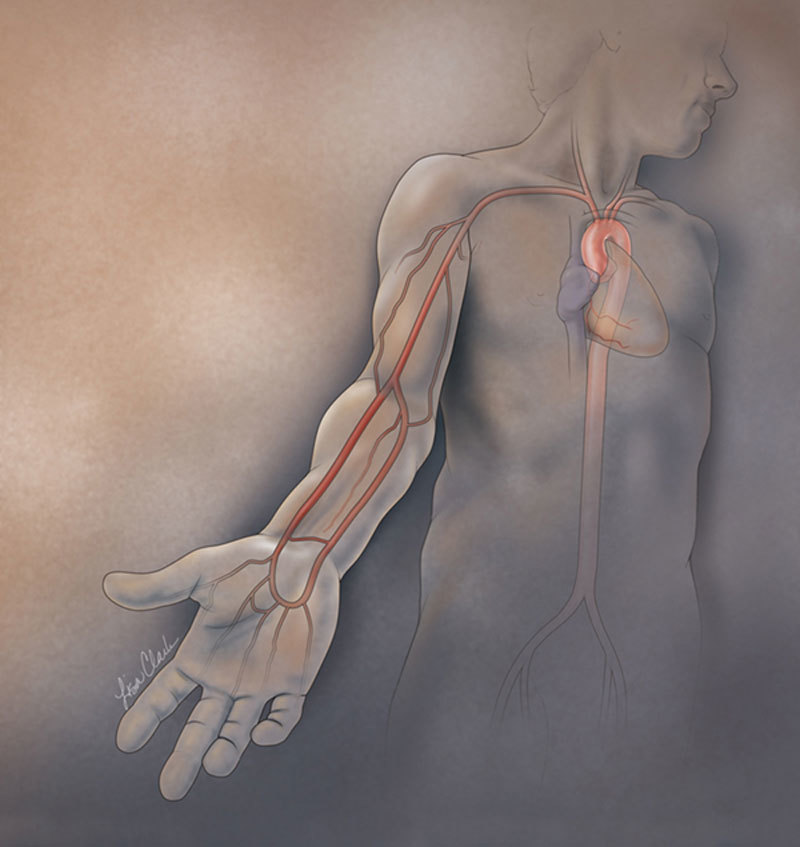

Помочь сосудам

При жаркой погоде даже у здоровых людей в крови снижается количество кислорода, она становится более густой и вязкой. Отсюда одышка, слабость и быстрая утомляемость. А если нет возможности отмокать в море или хотя бы бассейне, а надо топать в пыльный офис? Совет от кардиолога Тамары Огиевой:

— Привести сосуды (в том числе и головного мозга) в тонус можно так: принять 1 таблетку но-шпы, 1 таблетку глицина и 20 капель валокордина на полстакана воды.

Но-шпа снимает спазм и расширяет сосуды, глицин (аминокислота, улучшающая мозговые процессы) стимулирует работу клеток мозга, валокордин (корвалол, валосердин) оказывает седативное действие — успокаивает вообще и расслабляет напряженные сосуды и мышцы.

А народная мудрость (с которой кардиологи вполне согласны) советует в нестандартно жаркий период снять с себя все «закольцованные» украшения — цепочки, перстни, браслеты. Это освободит ток крови по мелким сосудам, что улучшит кровообращение в целом.